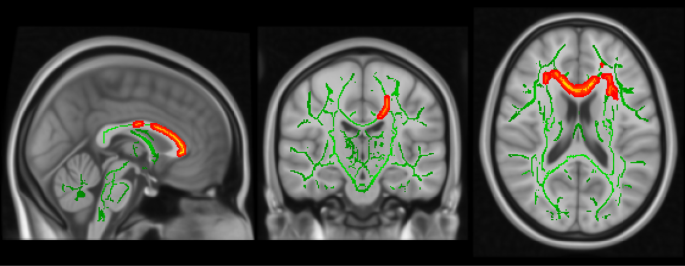

Diffusion Tensor Imaging Shows 4 Different Tracts Intermingled In Download Scientific Diagram